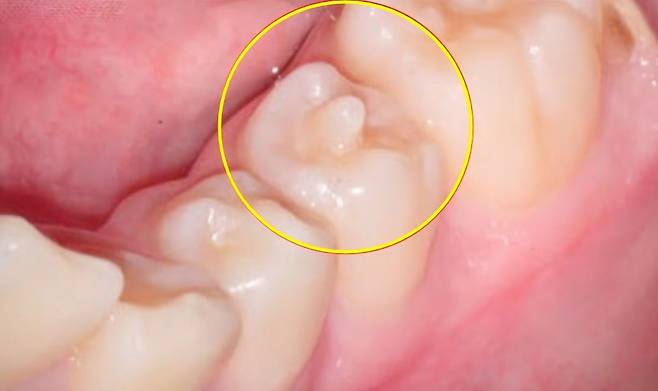

치아를 자세히 보면 씹는 면의 형태가 평평하지 않고 올록볼록하다. 윗니와 아랫니가 잘 맞물려 음식을 씹기 위해서다. 그런데 간혹 단순히 울퉁불퉁한 수준이 아니라, 씹는 면 중앙에 뾰족한 뿔처럼 생긴 돌기가 관찰되는 경우가 있다. 이를 치외치라고 한다. 치아에 작은 치아가 나와 있다는 의미다. 작은 어금니에서 자주 관찰되고, 유병률은 대략 3~5% 수준이다. 아시아인에서 조금 더 많이 발생하는 것으로 알려져 있다.

치외치는 일종의 기형치아다. 발생 원인은 알려지지 않았으나 유전적인 영향이 크다. 대개 유치를 뽑고 영구치가 나오는 시기인 11~13세 성장기 아동의 치아에서 발견된다.

문제는 단순히 모양만 뿔과 같은 형태인 것이 아니라, 치외치 내에 신경까지 따라 올라와 있다는 점이다. 평소 충치가 없고 관리를 잘하더라도 저작 활동만으로 치외치가 조금씩 마모되거나 부러진다. 이 경우 신경이 바로 노출되고, 세균이 침투하게 되는 것이다.